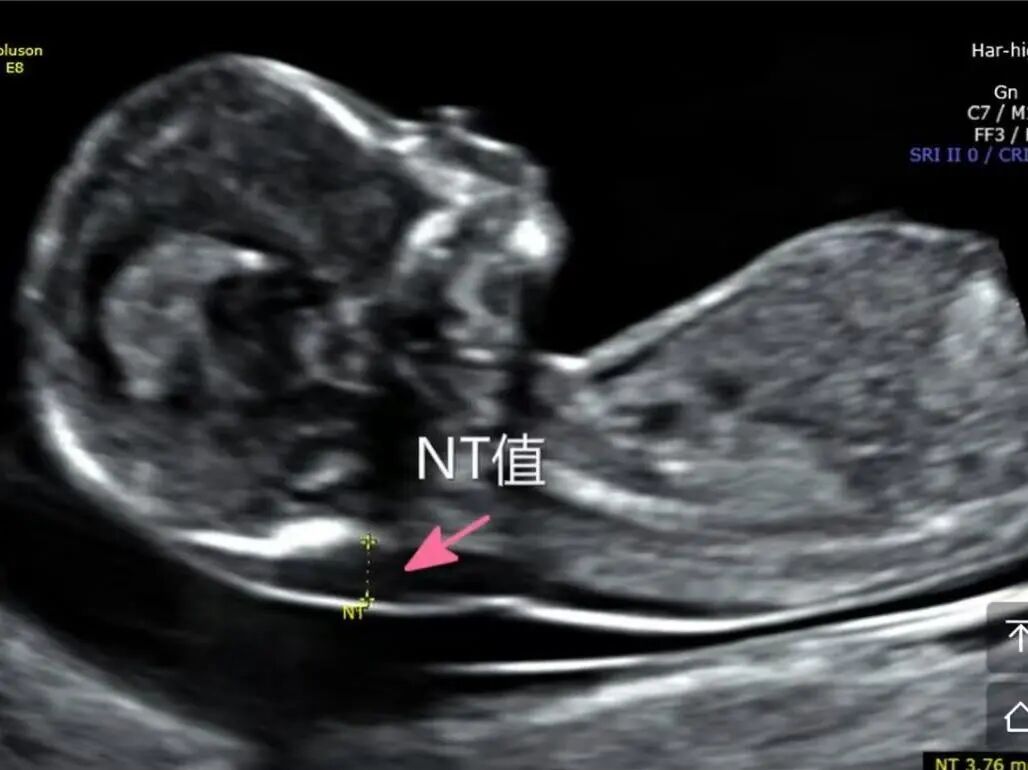

您是否也遇到过这些尴尬时刻?提重物时突然漏尿、运动时总觉下腹坠胀、更年期后总想跑厕所......这些信号可能在提醒:盆底肌需要关爱了。 盆底肌群如同"弹簧床",承托着膀胱、子宫等器官。妊娠分娩、雌激素变化、长期腹压增加等因素,都可能导致这张"网"松弛。若不及时干预,可能发展为: ▷ 盆腔器官脱垂(子宫/阴道膨出) ▷ 压力性尿失禁(咳嗽/大笑漏尿) ▷ 排便障碍(便秘/失禁) ▷ 性生活质量下降 【哪些人需要关注盆底筛查?】 ✓ 产后42天妈妈(尤其经阴道分娩) ✓ 频繁漏尿或排尿困难 ✓ 长期便秘/慢性咳嗽 ✓ 更年期女性 ✓ 性生活疼痛或下腹坠胀人群 【无创筛查新选择:盆底超声】 不同于传统指检,这项技术通过会阴体表扫描: ⏩ 多维度观察静息/收缩/用力状态 ⏩ 精准评估肌群损伤程度 ⏩ 动态捕捉器官位移情况 女性盆底三维多层显像 【检查须知】 ✔️ 避开经期 ✔️ 检查前排空膀胱 ✔️ 穿宽松裤装更方便 ✔️ 配合医生指令做缩肛/屏气动作 盆底超声检查 女性健康管理不该止于体检常规项。建议存在相关症状的女性,及时到正规医院妇产科或超声科咨询。早筛查、早干预,让盆底肌恢复应有的"托举力"。 注:部分图片来源于网络,如有侵权,请联系删除。 贵州航天医院超声科专家团队 吴艳辉 中共党员,超声科学科带头人、主任,主任医师 专业擅长:从事超声诊断工作约30年,对心血管、小器官超声、超声引导下介入等具有丰富的临床经验。 胡大海 超声科副主任,副主任医师 专业擅长:从事超声工作17年,对心血管、外周血管、浅表器官超声诊断等具有丰富的临床经验。 骆科美 中共党员,超声科副主任医师 专业擅长:从事超声诊断工作33年,对胎儿心脏及颅脑、妇产超声诊断、盆底超声等诊断具有丰富的临床经验。 刘 敏 超声科副主任医师 专业擅长:从事超声诊断工作20余年,对妇产科超声、心脏血管超声诊断具有丰富的临床经验。 贵州航天医院超声科简介 基本情况 贵州航天医院超声科配备多种超声检查设备(飞利浦彩超(IU-22、IU-Elite、HD11、Q5、Q7),迈瑞超声I9、DC-6、DC-8、GE-E8及床旁机,彩色超声诊断仪等),设有心血管诊室、妇产科诊室、腹部诊室、绿色通道、浅表小器官等检查室。 诊疗范围 科室业务覆盖腹部、泌尿、妇科、产科(常规、NT筛查、III级筛查超声检查及高危妊娠监护)、成人心脏、外周血管、浅表器官(包含甲状腺、乳腺、阴囊、眼睛等)、颅脑(小儿颅脑、成人颅脑)、小儿肺超、造影、盆底、腹直肌、肌骨神经等检查及各种介入引导。 专科特色 四肢血管超声检查、双胎产前筛查及超声监护、超声造影检查技术、介入超声临床应用、经颅脑实质超声辅助筛查诊断帕金森病、女性性早熟超声诊断、盆底超声检查等。 NT超声检查 超声介入引导 肝脏超声造影 甲状腺造影 颅脑超声帕金森辅助检查 乳腺超声造影 上肢动静脉造瘘超声检查 双胎超声筛查 下肢血管超声检查 右心造影 END